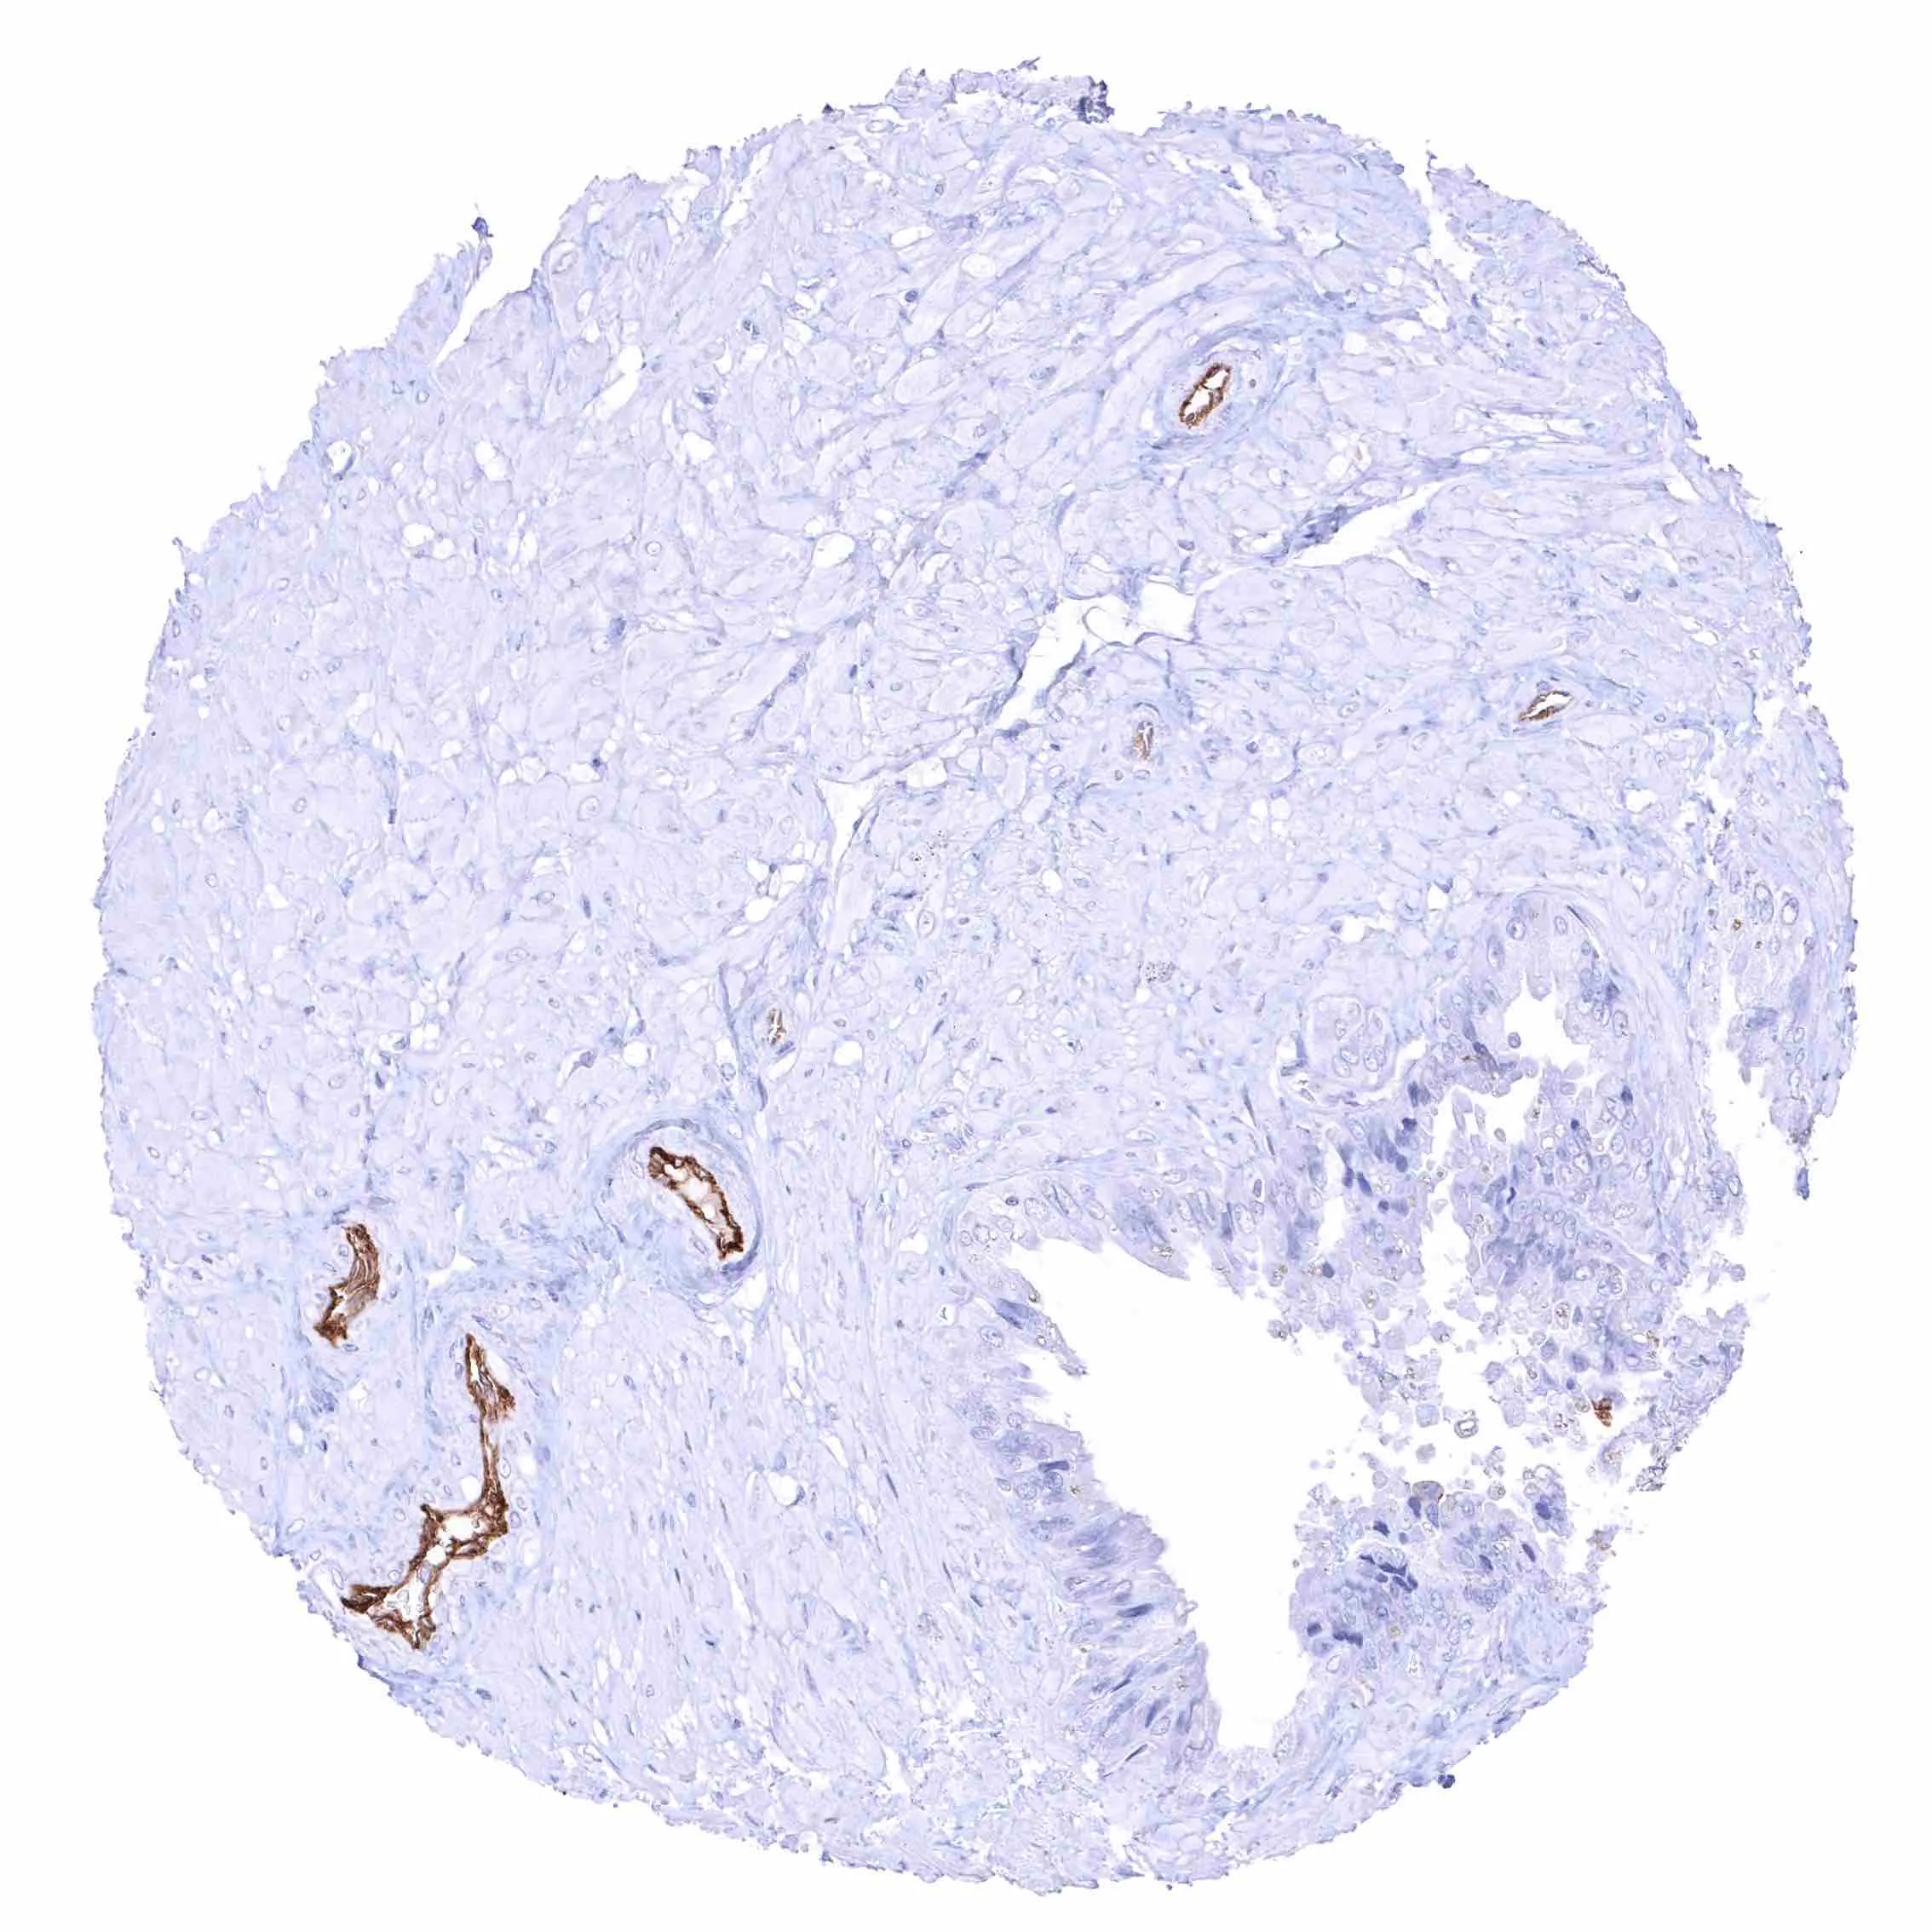

Prostate